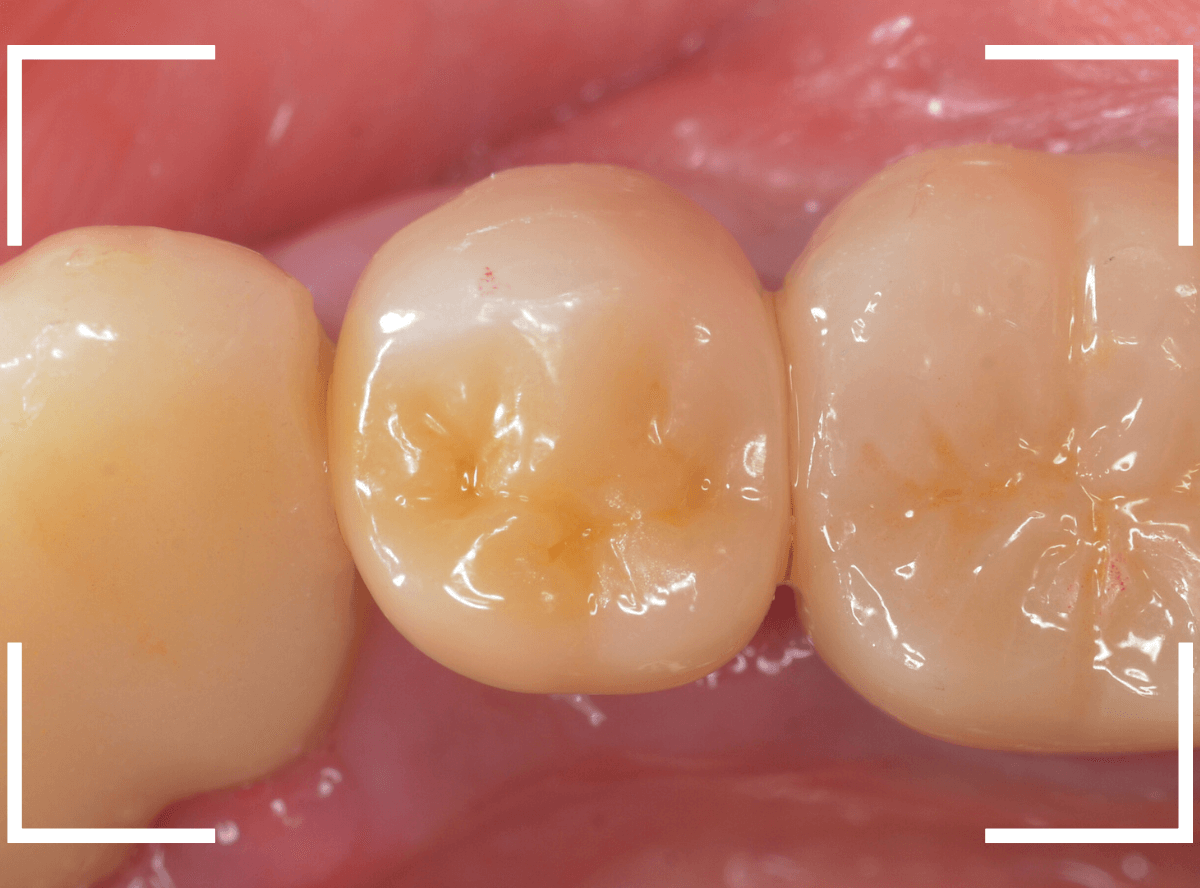

以前治療した、セラミック・インレーが破折してしまった患者さんです。

セラミック・インレーを修復した後に、抜髄(歯の神経を取る治療)をすることになってしまったそうで、今回は、さし歯(クラウン)で修復する事になりました。

最終setした状態です。

見た目も問題なく、患者さんにも満足いただけました。